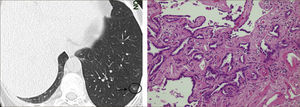

Sin embargo en los últimos años se han producido grandes avances en la oncología torácica, tanto en métodos diagnósticos, estudios anátomo-patológicos y moleculares y en el tratamiento, tanto médico como quirúrgico, que han hecho que el concepto de nódulo pulmonar solitario sea insuficiente para el manejo de los diferentes tipos de nódulos pulmonares (NP) que enfrentamos hoy en la práctica clínica.Figura 1

La masificación de los métodos de diagnóstico por imágenes, especialmente del TAC de Tórax, ha significado un importante aumento en la detección de NP pequeños, menores de 2cm, no visibles en la radiografía de tórax. Estos nódulos pueden ser tanto sólidos como sub-sólidos, cada uno tiene diferente comportamiento, velocidad de crecimiento y probabilidad de malignidad2,3 (Figuras 2 y 3).

El diagnóstico por imágenes mediante TAC de Tórax, cumple por tanto un rol fundamental en la identificación y caracterización de los nódulos pulmonares. Los cánceres pulmonares iniciales pueden presentarse como nódulos de diferente densidad: sólidos, cavitados, en vidrio esmerilado (VE: definidas como una intensidad discretamente mayor a la del parénquima pulmonar a través de la cual la vasculatura pulmonar es visible) o lesiones mixtas con componente sólido y VE. Figuras 2 y 33. En etapas más avanzadas los CPNCP se presentan como nódulos de mayor tamaño o masas (>3cms), sin embargo también pueden presentarse como lesiones consolidadas mal definidas, especialmente algunos adenocarcinomas productores de mucina. Estas lesiones pueden ser indistinguibles de una neumonía, pero a diferencia de estas persisten en el tiempo pese al tratamiento antibiótico 27,28.

Las lesiones Subsólidas tienen un mayor riesgo de malignidad que puede alcanzar un 18%51. Las lesiones subsólidas pueden corresponder a lesiones en Vidrio Esmerilado Puro (VE o GGO: Ground Glass Opacity) o a lesiones mixtas con un componente en VE y una zona sólida (Figuras 4, 5 y 6).

Asamura recientemente correlacionó también los hallazgos radiológicos con los histológicos en diferentes nódulos pulmonares pequeños. Las lesiones en VE puro corresponderían generalmente a Hiperplasia Adenomatosa Atípica (HAA), las lesiones mixtas (con componente en VE y sólido) a adenocarcinoma in situ y las lesiones mixtas en que el componente sólido sea mayor al 50% de la lesión corresponderían a adenocarcinomas invasores53.

Los nódulos en VE menores a 5mm generalmente corresponden a Hiperplasia Adenomatosa Atípica (HAA). Los nódulos en VE mayores pueden corresponder a HAA o Adenocarcinomas. Los CPNCP que se presentan como lesiones en VE puro (pure GGO) corresponden generalmente a adenocarcinomas in situ, adenocarcinomas tipo A en la clasificación de Noguchi54Figura 4.

Las lesiones mixtas (con componente en VE y sólido), son las que tienen la mayor probabilidad de malignidad, la que alcanza hasta un 63%51. Mientras mayor sea la proporción del componente sólido, mayor es la probabilidad de malignidad y peor el pronóstico. Estas lesiones corresponden a Adenocarcinomas micro invasores o invasores (Noguchi By C), Figura 4. Finalmente el desarrollo de un componente sólido en una lesión en VE o el aumento de la proporción del componente sólido en una lesión mixta en seguimiento indica su transformación en una lesión más agresiva50,51,53–57.